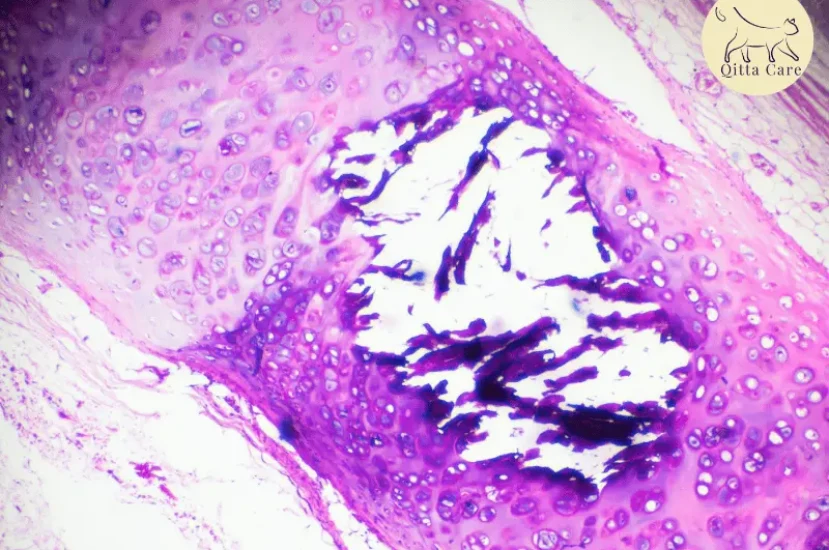

يتم تشخيص التهاب الأنف والقصبة الهوائية بناءً على الأعراض السريرية وتاريخ القط الطبي. قد يقوم الطبيب البيطري بإجراء فحوصات مخبرية لتأكيد وجود فيروس الهربس القططي-1.

2. التهاب القرنية القرحي : تقرحات عميقة في القرنية قد تؤدي إلى تمزق العين.